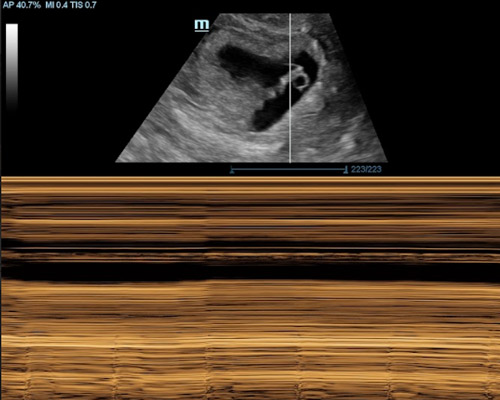

Our Scans

During a reassurance scan, you may see your baby’s heartbeat, movements, position, and general activity on the ultrasound screen.